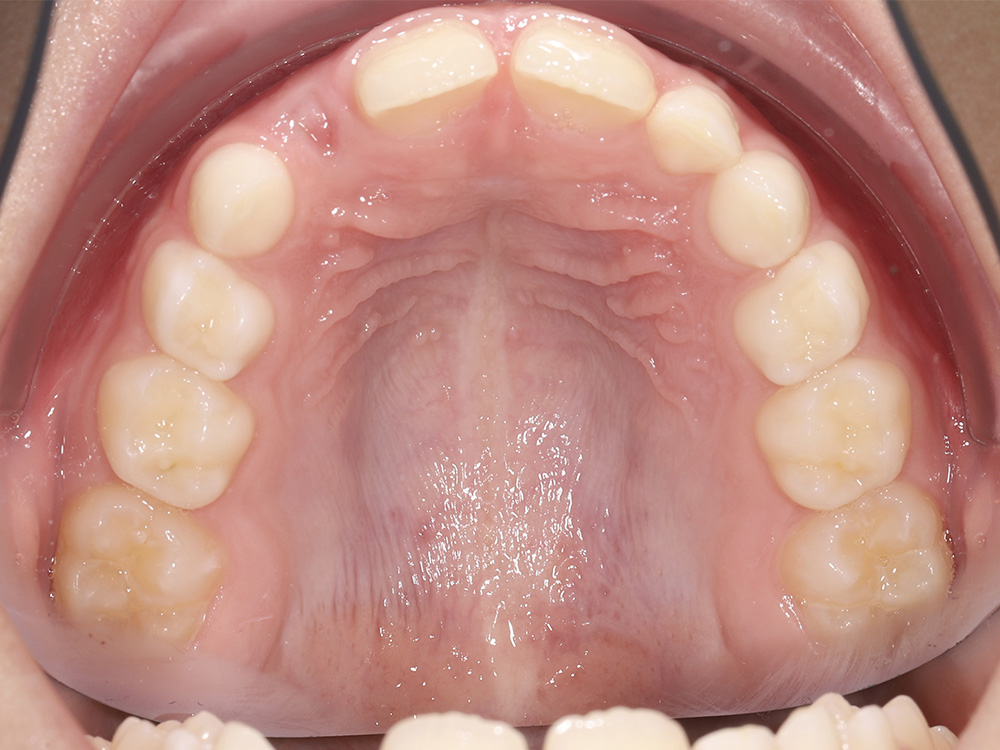

Создание условий для правильного прорезывания постоянных зубов при сужении зубных рядов у ребёнка